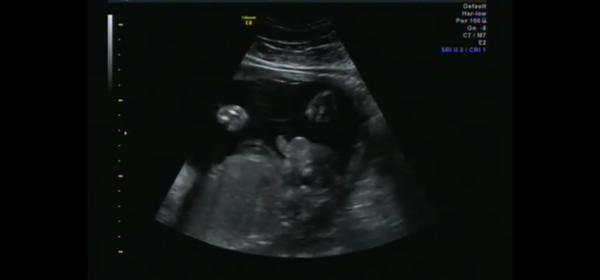

Holka nebo kluk? Matoucí výsledky ultrazvuku ve 26. týdnu

byla jsem na posledním screeningu, kde mi pan doktor řekl, že je to 100% holčička. Na tom by nebylo nic divného, kdyby mi celou dobu všichni netvrdili, že to je kluk, což dle ultrazvuku viz fotky mi připadá jako jasná věc. Fotky jsou z 26tt ze 4D. Moc děkuji za názory 😂

Já u tebe nevím, ona to holka klidně být může, víc by byl ten pytlík dole u zadečku, kdyby to byl kluk myslím... těžko říci...

Ja v tom vidim kluka 😃